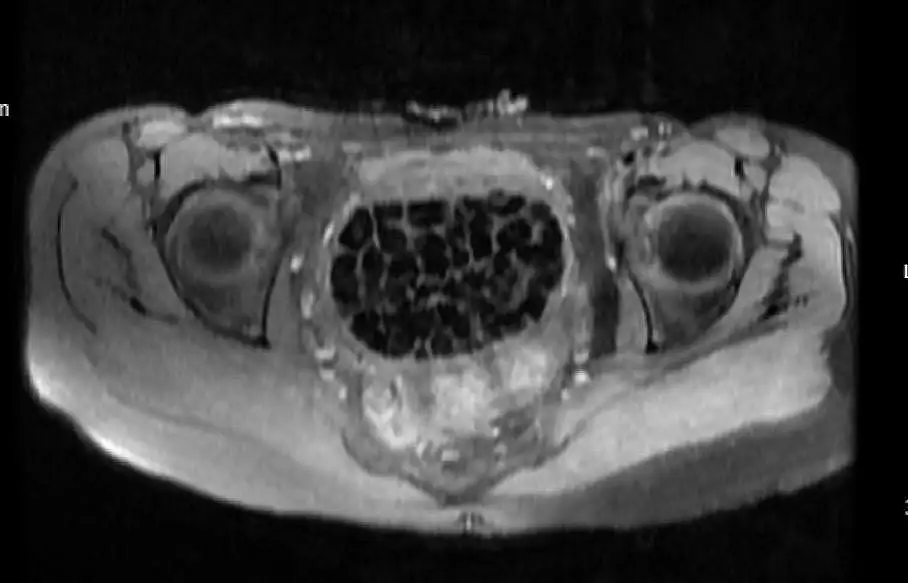

Hastasının durumuna yönelik konuşan Üroloji Uzmanı Doç. Dr. Erkan Erkan, "Hastamızın 2004 yılında doğduğunu ardından doğar doğmaz ekstrofi vezika dediğimiz 50 binde bir görülen bir anomaliden dolayı art arda ameliyatlar geçirdiğini öğrendik. 10 yaşında yine bir ameliyat geçirmişti, gerekli görüntüleme ve tetkiklerimizi yaptırdık. Normalde mesanesinin olması gereken yerin hemen arka kısmında taşlarla dolu bir kese olduğunu gördük, bunun üzerine ek görüntülemeler; MR çektirdik. Hastamız çelişkili açıklamalar almıştı, kendi radyolojik kliniğimiz ve edindiğimiz konsültasyonlarda taşların mesanede değil vajinal boşlukta oluştuğunu düşündük, bir planlama yaptık. Kadın doğum hocamızın da çabasıyla taşları tamamen temizledik ardından ileride normal bir hayat sürmesi bakımından oraya plastik cerrahi yaptık. 287 adet taş çıkardık, pratikte gerçekten görünce çok şaşırdık çünkü bu aynı zamanda literatürde çok nadir görülen bir olay. Biz ameliyata hazırlanırken de teorik olarak biraz araştırdık. Literatürde gördüğümüz kadarıyla buna benzer bu tanıma uyan bir vaka vardı. Literatürde sanırım yayınlanmış 2’nci vaka olacak. Farkındalık çok önemli, bilinçli bir hastamız vardı. Doğumsal anomaliyle doğan çocuklarımızda ileride bunlara bağlı bazı sıkıntılar çıkabileceğinin öngörülmesi lazım. İlgili tedavilerini alsalar bile düzenli takiplere gelmeleri gerekiyor. İleride eğer dikkat etmezse ki zannetmiyorum, tekrarlayabilir. Bu rahatsızlık ekstrofi vezikal epispadias durumu çok nadir bir durum" dedi.

Genç kızın uzun süredir devam eden karın ağrısı olduğunu söyleyerek sözlerine başlayan Jinekolojik Onkoloji Uzmanı Op. Dr. Emin Erhan Dönmez, "Mesane taşları olduğu düşünülerek daha büyük bir hastaneye refere edilmiş. Aramızda mini bir konsey yaparak muayene ettik. Vajen bir hazne görevi görerek orada durağan bir idrar, uzun süre beklediği için idrar içindeki minerallerde çökerek taşlar oluşmuş. Mesanedeki idrarın vajene akmış olabileceği ve vajende göllenen idrar nedeniyle taşların burada oluşacağını düşündük, ameliyatımızı planladık. Ameliyata tanı amaçlı girmiştik, sistoskopi (Mesane gibi idrar yollarını kapsayan kısımlardaki rahatsızlıkların teşhis ve tedavisinde kullanılan endoskopik bir yöntem) dediğimiz ameliyatı Erkan Hocam ile birlikte gerçekleştirdik. Önce mesaneyi bir görüntüledik, mesane tabanına yaklaşık 2-3 cm’lik bir alandan vajene fistülize olduğunu gördük. Mesaneden vajene geçtiğimiz esnada tüm vajenin taşlarla dolu olduğunu gördük. Tanı amacıyla girdiğimiz ameliyatta her şey de olağan gittiği için tedaviye geçtik. Taşların çıkabileceği kadar bir genişlik sağladık. Daha sonra yaklaşık en büyüğü 2,5 cm boyutlarında olan, irili ufaklı 287 tane taşı ameliyat esnasında çıkarmış olduk. Taşların tekrarlamaması için idrarın göllenmemesi, en azından dışarıya rahatça boşalabilmesi için vajinal rekonstrüksiyonu sağladık. Ameliyatta da herhangi bir problem yaşamadık. Literatürü Erkan Hocam ile birlikte değerlendirmiştik. Primer olarak vajende birikmiş olan bu kadar çok sayıda taşla ilgili bir makale görmedik, rastlamadık" dedi.